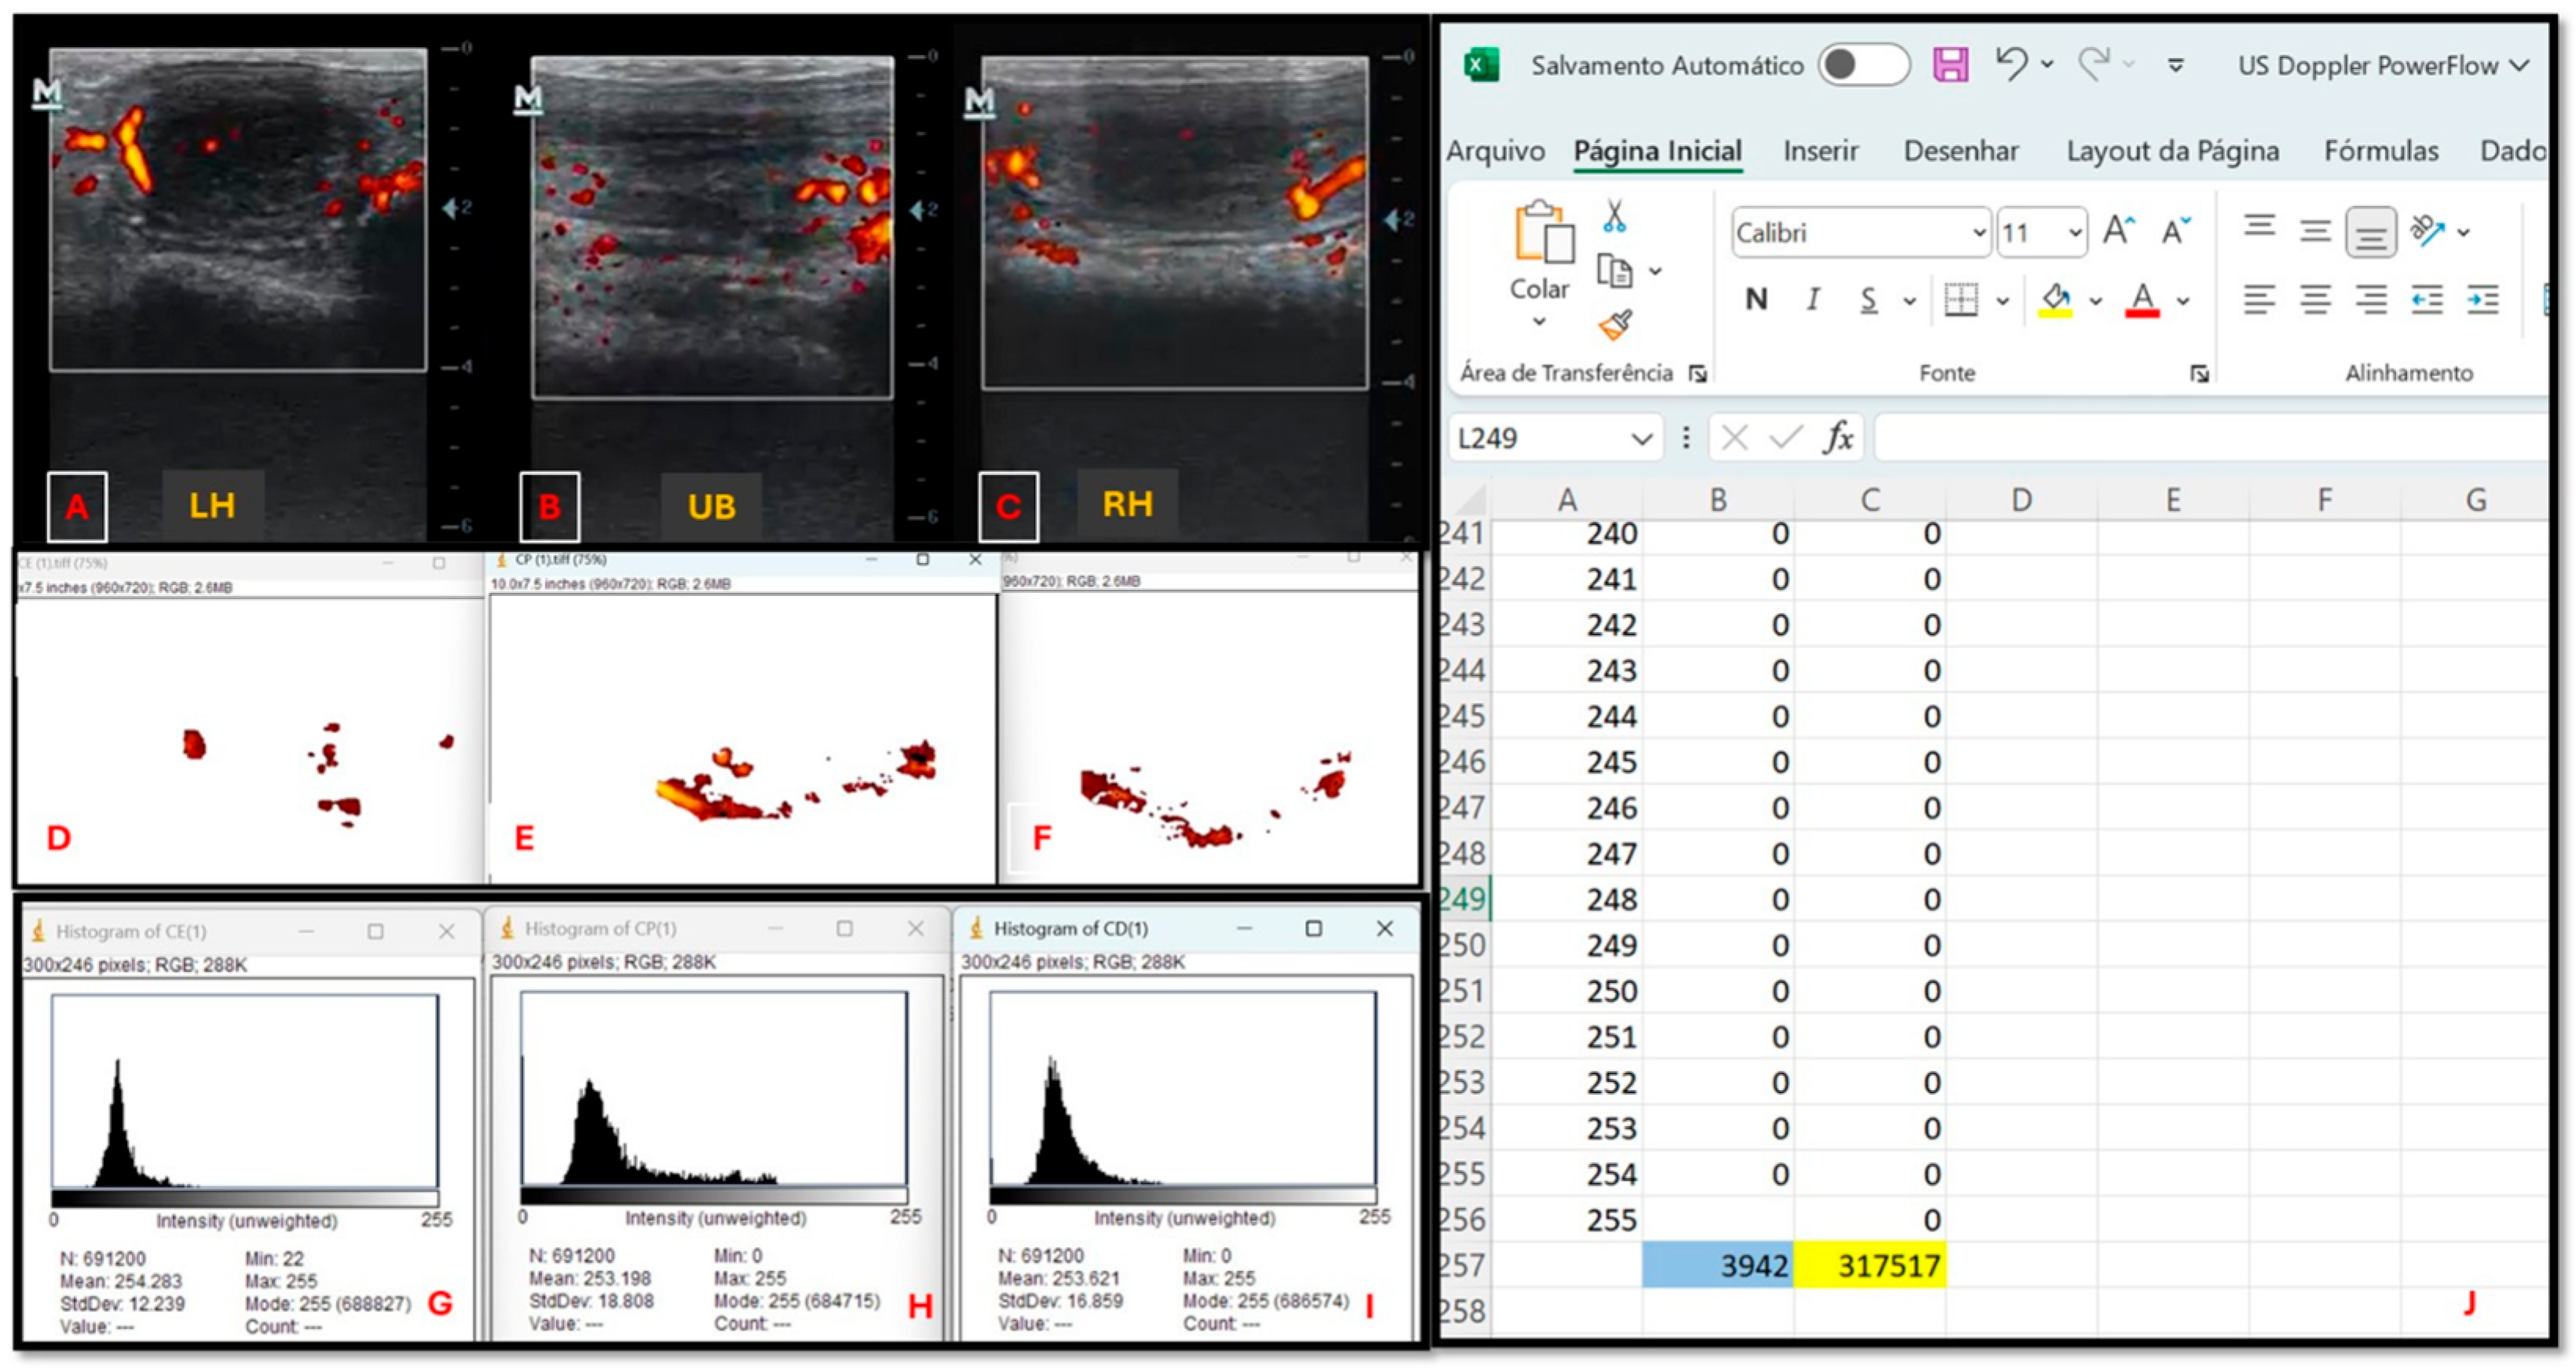

| n | Subjective Assessment | Number of Pixels | Intensity of Pixels | |

|---|---|---|---|---|

| Treatment Groups | ||||

| GC | 16 | Low perfusion a | 5212 ± 2452 a | 33,187 ± 170,984 a |

| GES | 15 | Low perfusion a | 5069 ± 2534 a | 436,207 ± 15,772,230 a |

| GEC | 14 | Mild perfusion b | 5475 ± 2856 a | 362,201 ± 208,170 a |

| Microbiological culture | ||||

| 0 | 16 | Low perfusion a | 5221 ± 2456 ac | 333,600 ± 171,370 ab |

| F | 4 | Low perfusion ac | 4187 ± 1441 bd | 276,727 ± 109,125 b |

| G+ | 6 | Mild perfusion b | 5480 ± 2101 ac | 357,362 ± 155,629 ab |

| G− | 9 | Mild perfusion bc | 5837 ± 3207 c | 379,045 ± 235,528 a |

| M | 10 | Low perfusion a | 5015 ± 2763 ad | 373,168 ± 452,380 a |

| Endometrial cytology | ||||

| Negative | 33 | Low perfusion a | 5048 ± 2257 a | 331,502 ± 187,156 a |

| Moderate | 10 | Mild perfusion b | 6013 ± 3565 b | 429,380 ± 452,930 b |

| Severe | 2 | Mild perfusion b | 4673 ± 1633 a | 297,283 ± 122,428 a |

| Endometrial biopsy | ||||

| I | 2 | Low perfusion a | 4326 ± 1237 a | 288,050 ± 103,864 a |

| IIA | 13 | Mild perfusion b | 6013 ± 3420 b | 415,687 ± 413,469 b |

| IIB | 18 | Low perfusion a | 4885 ± 2078 a | 330,696 ± 198,668 a |

| III | 12 | Low perfusion ab | 4885 ± 2079 a | 325,753 ± 159,811 a |